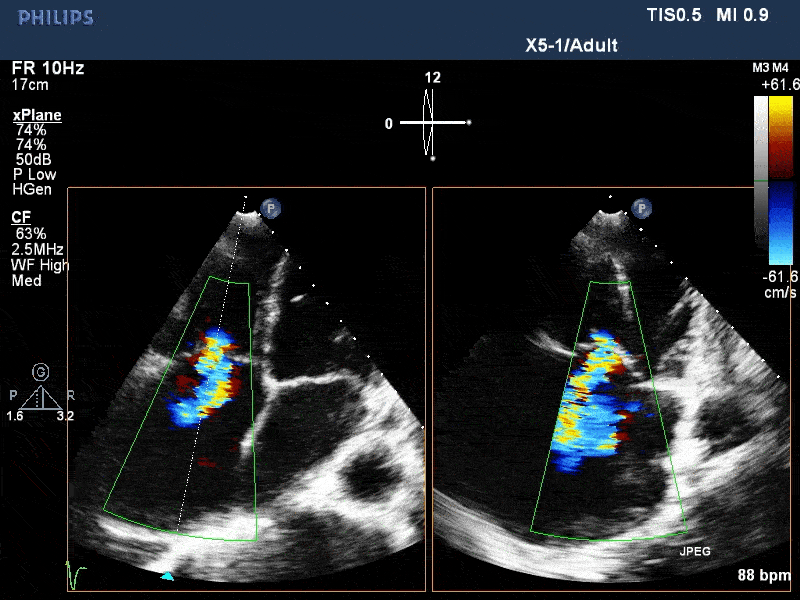

术前与术后即刻三尖瓣反流比较